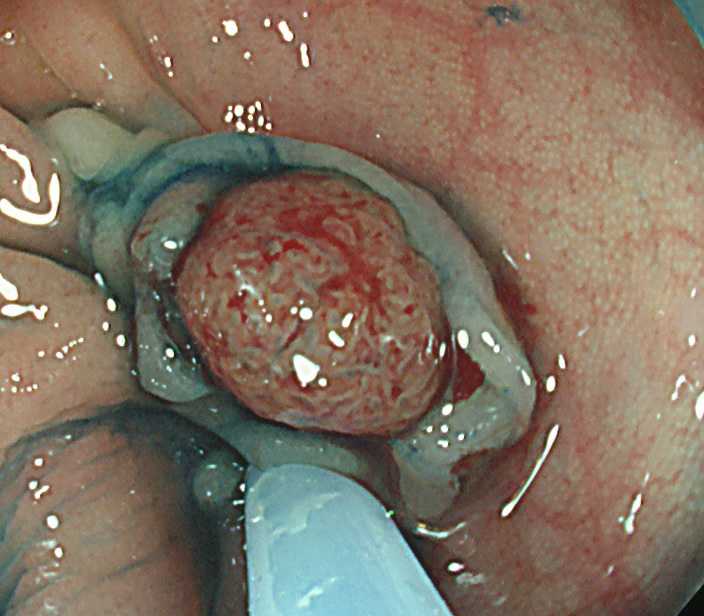

実際の写真です。

「生切り」なので、当然、内視鏡中(切除時)は出血します(患者さんが不安になります)。しかし、出血は数分で止まり、晩期出血は、まずありません。

取り残しを防ぐために、周囲に十分な余裕を持って大きく切除する必要があります(「ジャスト・サイズ」の傷では境界線上に腫瘍細胞が残ります)。そのために独特の「コツ」が必要で従来の方法よりも技術的に難しく時間がかかります。